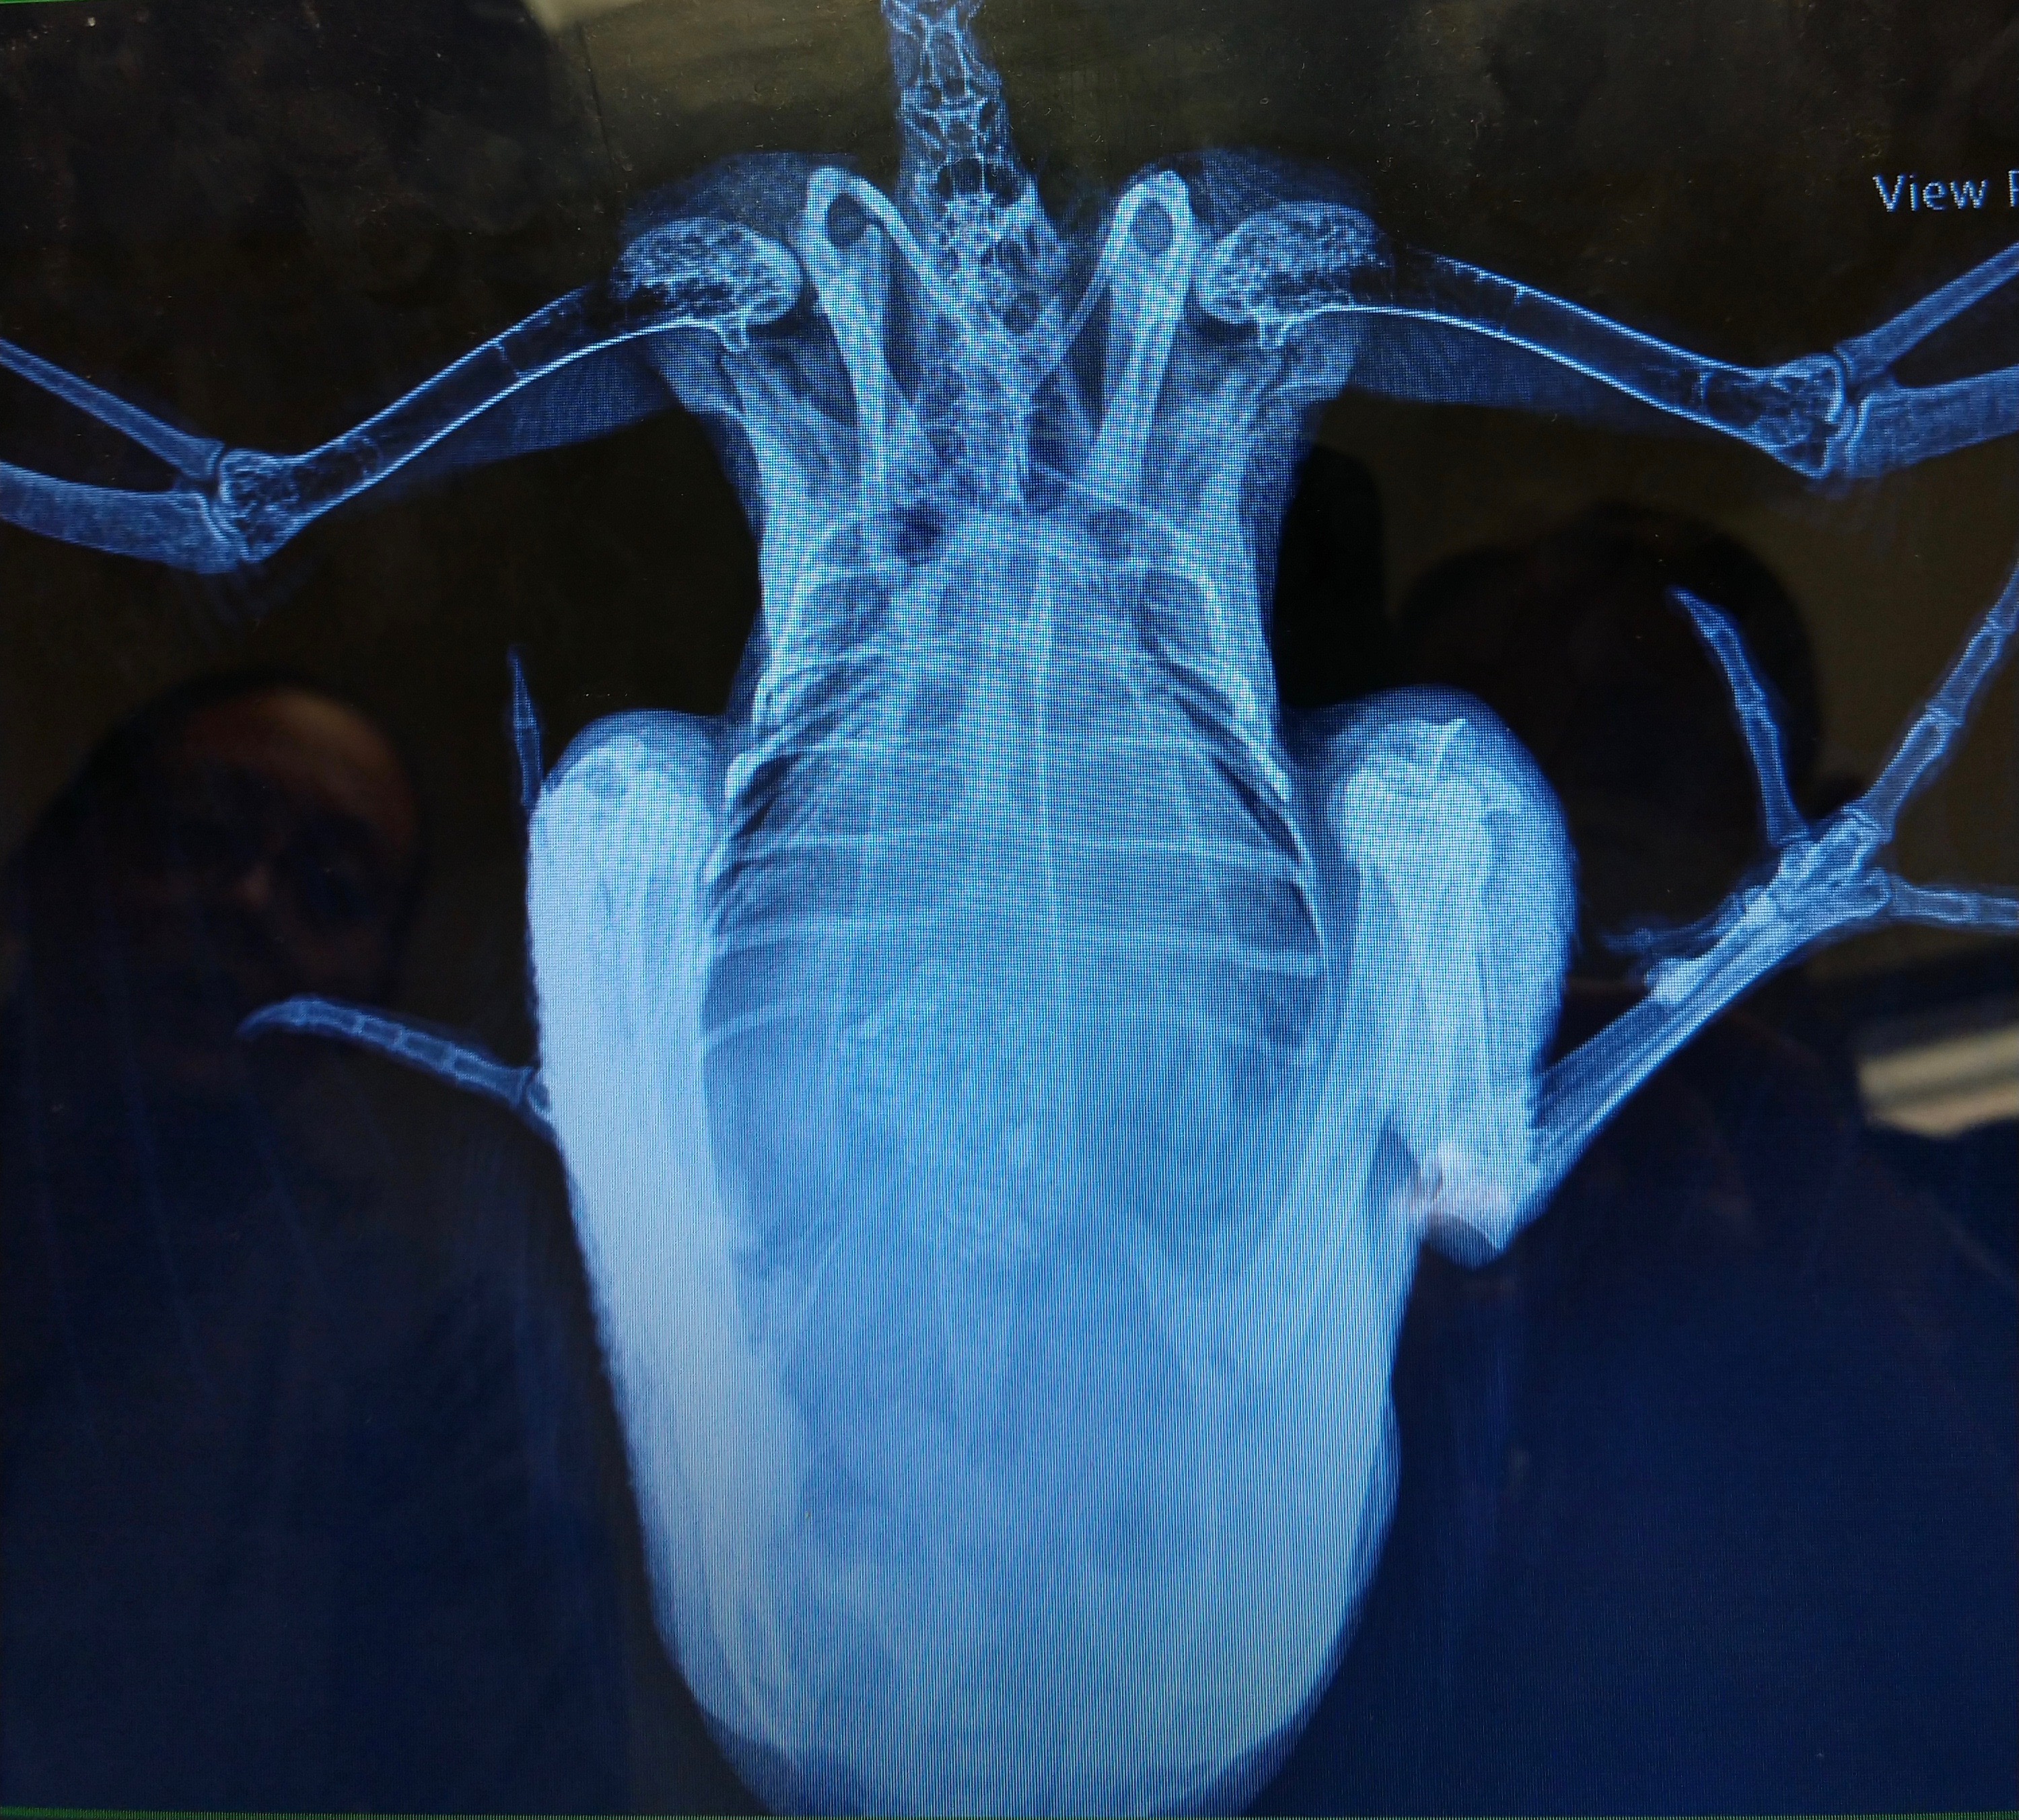

I noticed one hen laying down and not getting up. I found what I thought was broken yolk on her feathers around her bottom. I ultimately assumed an egg broke in her which I’ve dealt with many times. I scheduled emergency vet appointment with our avian vet for 6 pm. By then her leg is splayed out to the side, she’s deteriorated and seems more uncomfortable and won’t stand. They do X-rays and vet comes back in and says she has good and bad news (which should have been good and worse news). She didn’t have an egg break in her but looks to have eaten construction staples. As vet is showing me X-rays, tech comes in and says the leg or hip is confirmed dislocated. I decided to keep her hospitalized until Friday (when vet that could do surgery returned) for pain management and she received CaEDTA to absorb the heavy metals, next daywas eating and drinking on her own, and seemed to be perking up. Today she underwent a procedure to try to remove the staples using a scope with some robotic attachment, but they only were able to remove 1 of 8 without risking damage to stomach walls because they were embedded. They also popped leg/hip back in.

I’m picking her up tomorrow and she’s coming home on lactulose to see if it will help her pass the staples and back in 3-4 weeks for X-rays and another procedure/surgery with the scope to try to remove. I’m not understanding how if embedded they’d come out, going to ask more tomorrow when I get her, but moreso wondering if anyone has gone through anything similar. She was under anesthesia for 3 hrs, they said she did great but I’m also $2k in and I don’t want to keep putting her under, nor do I want to keep spending $1-2k to try to remove them. – Sarah Minderlein

Dr Bowes: I’m glad you took her to a vet but, unfortunately, I agree with your feeling that embedded staples will not come out on their own. Sometimes small screws or other objects can pass on their own, but these staples are fine with two sharp ends that will easily become lodged and not move down her digestive tract. Surgery is required to extract them.